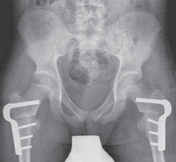

34. Once there is clinical and radiographic evidence of union and consolidation of the osteotomy, all restrictions can be lifted (

FIG 5

).

A

B

FIG 5 • Postoperative AP and lateral radiographs.

36. If adequate correction is achieved, ambulatory patients can expect to experience noticeable benefits in the appearance of their gait. Whether there are measurable functional improvements is less clear.